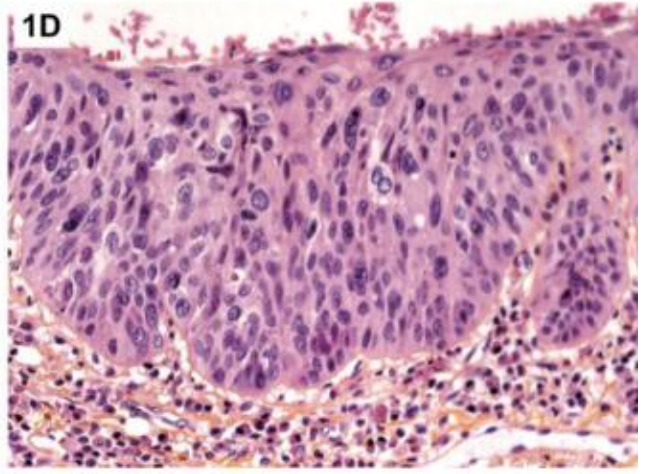

Dysplasia

—> Dysplasia

Dysplastic signs

irregular stratification

nuclear and cellular pleomorphism

hyperchromasia

loss of polarity

abnormal mitotic features

abnormal mitosis

arrow= normal

down= normal